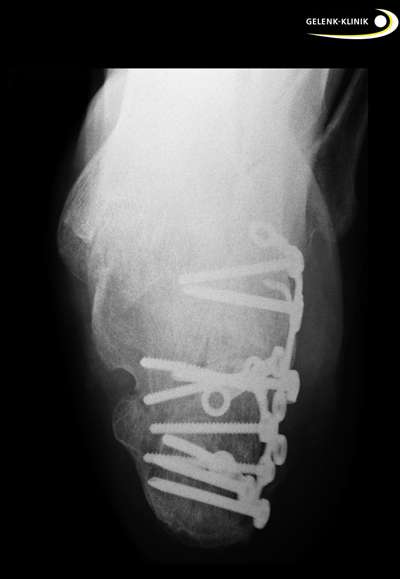

Die Entscheidung über die Art der Behandlung der Calcaneusfraktur erfolgt im Rahmen der Erstvorstellung im Notfallkrankenhaus. Dabei wird der klassische Fersenbeinbruch selten übersehen: Er ist einfach zu diagnostizieren. Die frühe Versorgung erfolgt häufig durch eine operative Stabilisierung der Fragmente mit Schrauben und Platten. Die Qualität dieser Versorgung ist für die Langzeitprognose und spätere Belastbarkeit des Patienten entscheidend.

Metallplatten am äußeren Calcaneus halten das wiederhergestellte Gelenk bis zur Knochenheilung in der richtigen Position. Allerdings ist der Fersenbeinknochen (Calcaneus) auf Grund der hohen, auf diesen Knochen wirkenden Kräfte, schwierig zu versorgen.

Metallentfernung nach Fersenbeinfraktur

Nach Fersenbeinbrüchen kommen außer der Arthroskopie auch eine Metallentfernung der Platten am Außenknöchel in Frage. Sehnen und Weichteilreizung, besonders bei Restfehlstellung, können störende Beschwerden im unteren Sprunggelenk verursachen. Insbesondere bei Knickfuß-Stellung ist die Metallentfernung ein wichtiger Gesichtspunkt, wenn noch chronische Schmerzen in der Fersenregion auftreten. Das außen am Fersenknochen angebrachte Plattenmaterial kann durch seine Lage die Bewegungsabläufe stören.